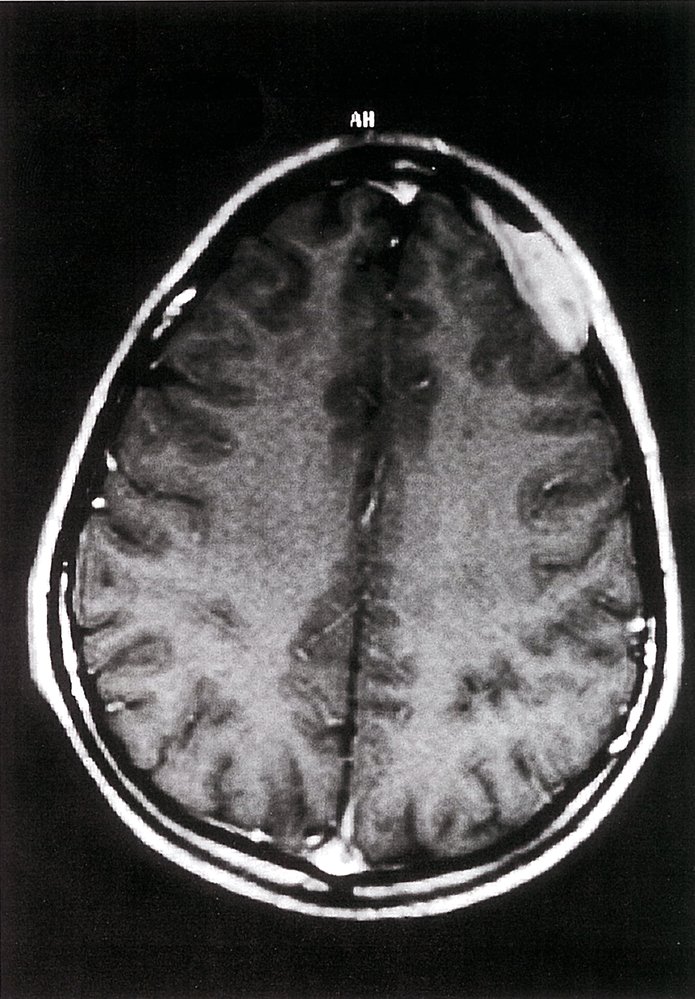

Langerhans cell histiocytosis

• Lytic lesion consisting of Langerhans and immune cells

• Peak incidence: 5–10 years

• Most commonly in the skull

• Painful swelling

• Pathologic fracture

• X-ray: osteolytic lesions with or without marginal sclerosis

• Typically, solitary lesions

• May manifest with rash and recurrent otitis media with mastoid swelling

• Lesions near the sphenoid, orbital, ethmoid, or temporal bones require treatment with vinblastine and prednisone.

• Description: : a rare disorder caused by clonal proliferation of Langerhans cells (antigen-presenting cells) [11]

• Epidemiology: : peak incidence between 5 and 10 years

• Clinical features

• Osseous lesions (90%): pain and/or swelling, pathological fractures

• Localization: skull (most common site), femur, vertebra, mandible, ilium, ribs

• Can cause recurrent otitis media if the mastoid bone is involved

• Unifocal or multifocal

• Systemic manifestations (less common)

• Skinrash: brown to purple papules and/or eczematousrash

• Hepatomegaly and/or splenomegaly

• Lymphadenopathy

• Bone marrow infiltration

• Hypopituitarism that typically manifests as central diabetes insipidus

• Exanthema

• Diagnostics

• Normal calcium levels

• Biopsy (confirmatory test): proliferation of Langerhans cells (polygonal cells with coffee bean-shapednucleiand eosinophilic cytoplasm) ; [12][13]

• Electron microscopy: Birbeck granules (tennis racket-shaped or rod-like structures) in the cytoplasm

• Immunohistochemistry: cells are positive for S100, CD1a, and/or CD207

• Treatment

• Solitary bone lesions in low-risk anatomical regions

• Asymptomatic lesion: a wait-and-watch approach may be appropriate

• Symptomatic lesion: curettage and/or excision (as a part of biopsy)

• Bone lesions in high-risk anatomical regions (e.g., lesions involving the odontoid process or regions of the skull other than the vault), multifocal bone involvement, or systemic manifestation: vinblastine and prednisone